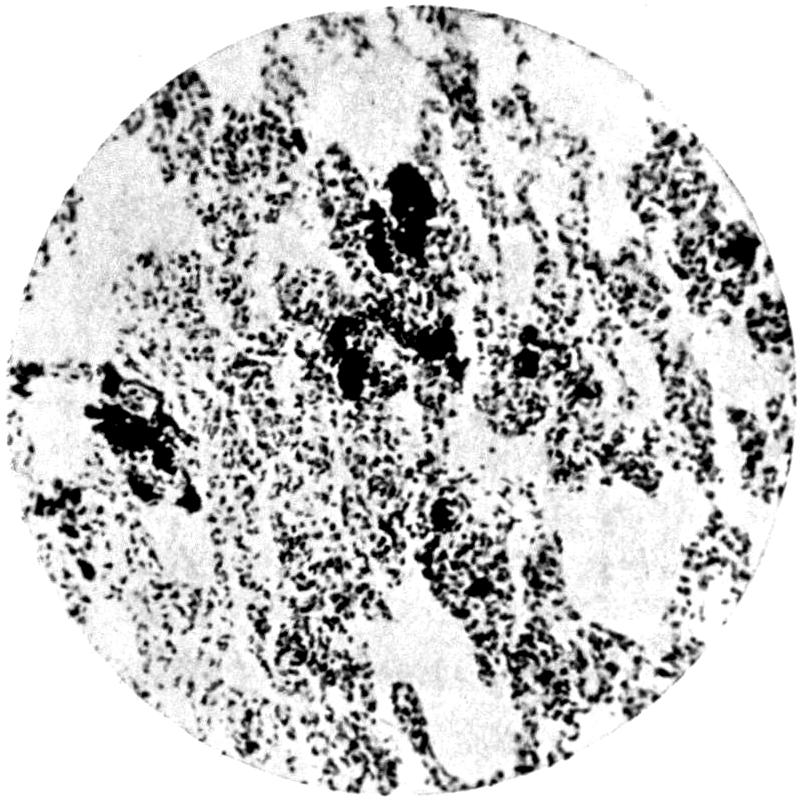

Plate I. 92

Plate II. 93

Plate III. 95

Plate IV. 276